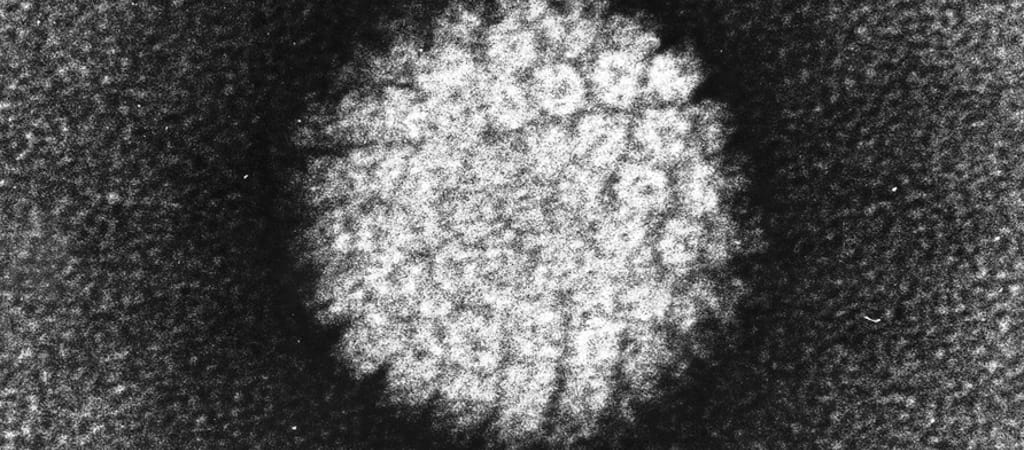

A HPV rendkívül elterjedt kórokozó, amely rendellenes sejtosztódást, sejtburjánzást okozhat a szervezet laphámfelületein, a kezeken, lábakon, a hangszalagon, a szájüregben és a nemi szerveken. A méhnyakrák a világ egyik súlyos egészségügyi problémája, évente mintegy félmillió új esetet fedeznek fel. A méhnyakrák a második leggyakoribb rosszindulatú daganat, és a harmadik helyen áll a nők daganatos halálozásában a világon.

Világszerte két oltóanyagot alkalmaznak, amelyeket a HPV néhány típusa ellen fejlesztettek ki, ezek védelmet nyújtanak a 16-os, illetve 18-as típusú humán papillomavírussal első alkalommal történő fertőzés ellen. Az oltások a vírussal már fertőzöttek számára nem nyújtanak semmilyen védelmet.